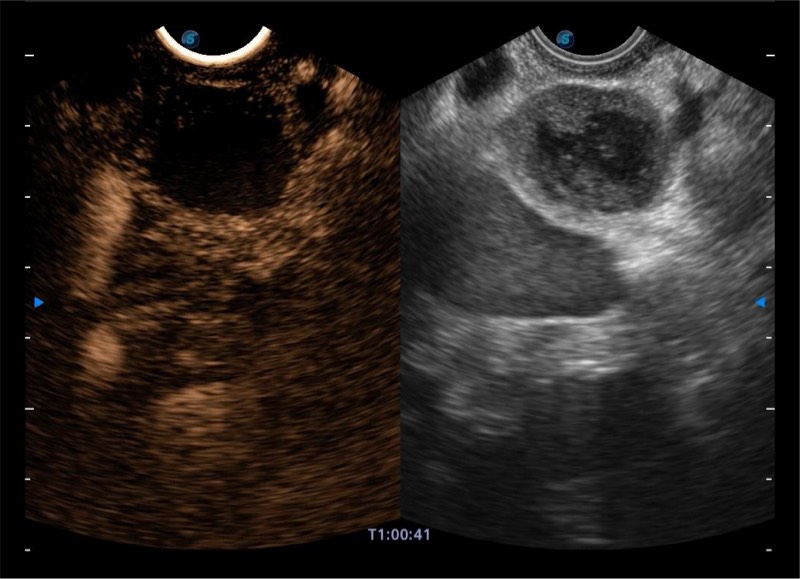

基于二十年的超声技术积累,16877太阳集团提供了最新一代的独立超声主机,在提供高质量图像的同时满足多学科使用。具备常见多普勒技术并提供弹性成像、声学造影等高端影像技术。新一代传感器具有更强的抗干扰能力并减少图像伪影。

4-12MHZ宽频输出